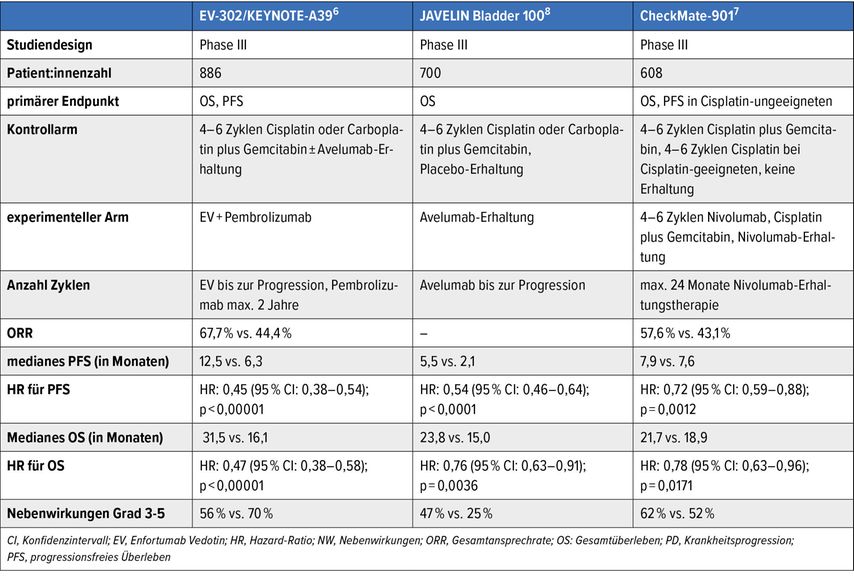

Der lokal fortgeschrittene und metastasierte Blasentumor stellt weiterhin eine therapeutische Herausforderung dar. Die Prognose ist trotz jüngster Fortschritte in der Systemtherapie weiterhin meist schlecht. Die Wahl der Erstlinienbehandlung orientiert sich seit Zulassung der Kombinationstherapie mit dem Antikörper-Wirkstoff-Konjugat (ADC) Enfortumab Vedotin (gerichtet gegen Nectin-4) in Kombination mit dem PD-1-Checkpoint-Inhibitor Pembrolizumab (EV+P) an der Tauglichkeit für diese Kombination vs. Nicht-Tauglichkeit.

Das mediane OS konnte mit dieser Kombination signifikant auf knapp 34 Monate im Vergleich zu 16 Monaten mit alleiniger platinhaltiger Chemotherapie ± IO-Erhaltung gesteigert werden. In der Studie waren auch Patient:innen mit schlechterem Allgemeinzustand (bis ECOG 2) und Patient:innen mit reduzierter Nierenfunktion (GFR ≥30ml/min) eingeschlossen. Ein Update mit einem Follow-up von nun 2,5 Jahren zeigt, dass die Patient:innen, die eine komplette Remission (CR) erzielen, auch längerfristig in einer CR bleiben.6

Bei Nicht-Tauglichkeit für EV+P stellt für Cisplatin-geeignete Patient:innen die Kombination aus Cisplatin+Gemcitabin+Nivolumab analog der Studie CheckMate-901 mit ebenfalls signifikantem OS-Vorteil im Vergleich zur alleinigen Chemotherapie eine Alternative dar. Für Patient:innen, die nicht fit für Cisplatin, jedoch fit für Chemotherapie sind, kann die Kombination aus Carboplatin+Gemcitabin mit anschliessender Erhaltungstherapie mit dem PD-1-Immuncheckpoint-Inhibitor Avelumab (Studie JAVELIN 100 Bladder) eingesetzt werden.7

Tab. 1: Zusammenfassung der Ergebnisse der Studien KEYNOTE-A39, JAVELIN Bladder 100 und CheckMate-901